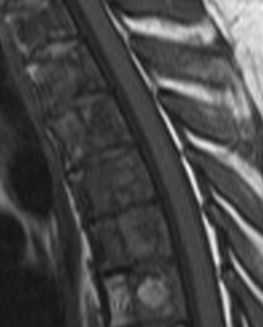

Изменения сигнала по типу MCh3 встречаются наименее часто и характеризуются гипоинтенсивным сигналом на T1- и Т2-ВИ на МРТ (рис. 3) [10]. Гистологически этот тип не изучался. На микро-КТ выявляются изменения, связанные с повышением уровня образования костной ткани и снижением ее резорбции [11]. На изображениях, полученных при проведении рентгенографии и мультиспиральной компьютерной томографии (МСКТ), этот тип характеризуется значительным уплотнением костной ткани — остеосклерозом [19, 20].

Рис. 3. Изменения на МРТ по типу MCh3. 1 — гипоинтенсивный сигнал на T1-ВИ; 2 — гипоинтенсивный сигнал на Т2-ВИ.